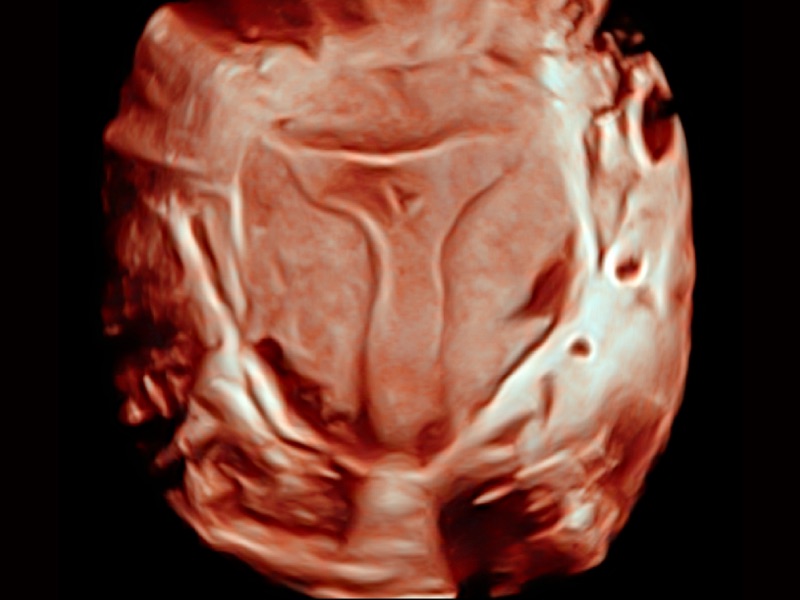

妇产科应用

三维光影成像技术采用新型的渲染方式,增强边缘信息,使得轮显示清晰完整,为临床提供丰富、直观的三维结构,提供临床诊断准确性。